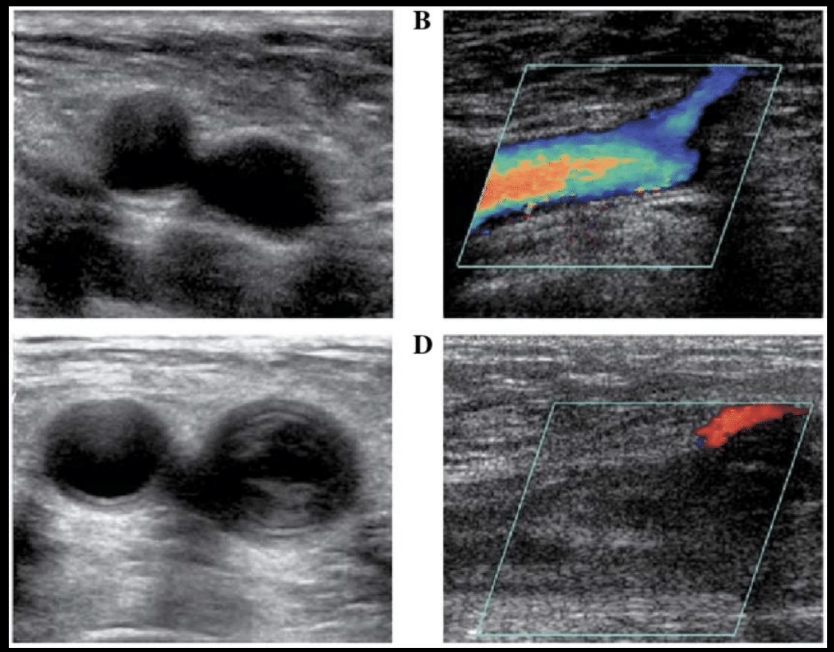

Hallazgos del doppler en sistema venoso

A

Vaso no compresible

Vena ecogénica

Ausencia de flujo

*Imagen arriba es normal, abajo es anormal